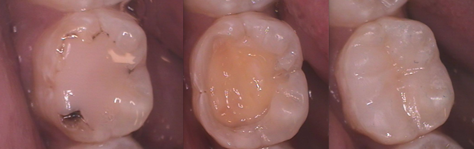

In a previous article, we compared the use, handling and other properties of three different composites. Even if you’re happy with what you’re using, it always benefits us to know the trends and what’s available “out there.” The ultimate goal of your composite material is to replace the biological, functional, and esthetic properties of healthy tooth structure.

If you had to pick only one composite to have in your office, your best bet would be a hybrid like Venus Diamond. You can see a comparison of Venus Diamond and Estelite Omega here. If you want creamier feel, another great choice is Venus Pearl. Needless to say there are a lot of other choices out there, so if Venus Diamond or Venus Pearl are not the right fit for you, try some others. It is hard to go too wrong as long as you stick with a major manufacturer.

Want a bulk fill without the need for special handpieces? Then give Tetric EvoCeram bulk fill a look. If, on the other hand, you’d rather add a composite for high esthetics, then give Estelite Omega a try; you’ll likely be amazed at what you can achieve with it. Are there other highly esthetic composites out there? Sure, but hands-down, our pick would be Estelite Omega.